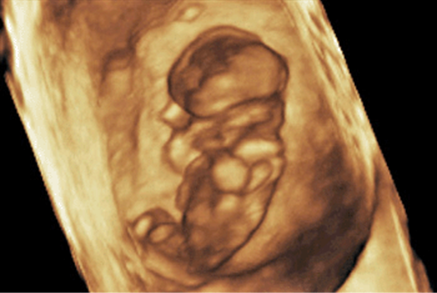

FIGURE 8–7. Three-dimensional sonogram of 12-week fetus showing normal umbilical cord fetal abdominal insertion. The physiologic herniation of bowel into the base of the cord that can be seen between 8 and 12 weeks should be completed by 12 weeks. (Courtesy of Philips Healthcare.)